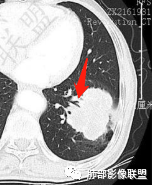

一般来讲,鳞癌收缩力弱,胸膜凹陷及牵拉少见,空洞坏死多见,而此例出现了“胸膜凹陷”,如下图:

这种特点在鳞癌比较多见  周围型鳞癌经常这个形态,外周有类似喇叭样收缩形态,考虑周围型鳞癌引起局部肺不张,所以有远侧内收而缺乏侧面收缩力。

回头看发现肿块近肺门侧边缘清楚,而远肺门侧边缘模糊,多考虑肿块阻塞支气管引起的阻塞性炎症,支持周围性鳞癌引起局部肺不张观点,两者形态相似,易与胸膜凹陷征混淆,小编认为,因肺不张为实变的肺组织,而胸膜凹陷为脏层胸膜受肿块牵拉凹陷形成的含液腔隙,故鳞癌形成的“胸膜凹陷”其密度较高,多为实性密度,而真正的胸膜凹陷征其内部密度较低,多为液体密度。